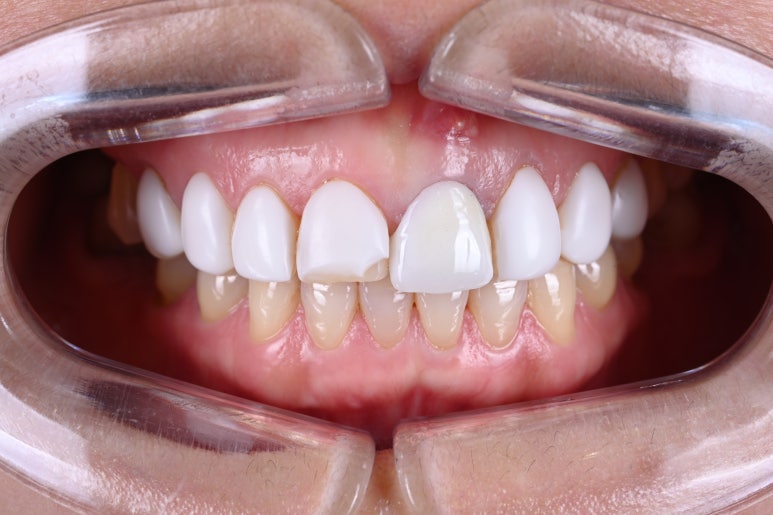

최소한의 치아 다듬기가 필요합니다.

압구정 치과 라미네이트를 붙이기 전 치아를 다듬은 모습입니다.

이게 정말 끝입니다.

어쩌면, 치아가 더 예뻐졌다고 생각하실지도 모르겠습니다. (?!)

수직, 수평 모양을 맞추고 날카로운 부위를 둥글리는 과정 정도로 이해해주시면 됩니다.

또한 표면을 매끈하게 만들어 제작된 레브네이트가 치아에 딱 잘 적합되게 하는 과정이지요.

스크롤을 위아래로 오르락 내리락 하시면서 확인해보세요!

기술의 발달로 라미네이트는 더 강해지고 더 얇아져, 치아를 폴리싱 하는 정도만 손보아도 라미네이트를 제작할 수 있게 되었습니다.!!